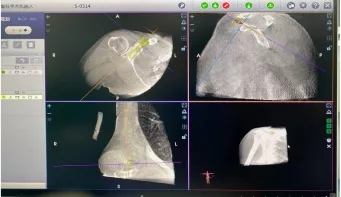

´îÅäOÐͱ۵ÄÌìçá?¹Ç¿ÆÊÖÊõ»úеÈË¿ÉÔÚ15ÃëÄÚ»ñÈ¡ÊÖÊõÇøÓòµÄÈýάӰÏñÊý¾Ý£¬£¬£¬£¬£¬Í¼ÏñÇåÎúÇÒ·øÉäÁ¿µÍ£¬£¬£¬£¬£¬Ï൱ÓÚΪÊÖÊõÅ䱸Á˸߾«¶ÈµÄÈËÌå¡°±±¶·¡±µ¼º½£¬£¬£¬£¬£¬ÈòÙ×÷¸ü¾«×¼¡¢¸üÇå¾²¡¢¸ü΢´´¡£¡£¡£¡£¡£¡£

OÐͱ۵¼Èë»úеÈËÈýάÊý¾Ý¾ÙÐо«×¼ÊÖÊõÉè¼Æ

ÔÚÕⳡ¸ß¾«¼âµÄÊÖÊõÖУ¬£¬£¬£¬£¬Ììçá?¹Ç¿ÆÊÖÊõ»úеÈËÓëOÐͱÛÍŽḨÖú£¬£¬£¬£¬£¬Ò»Åļ´ºÏ¡£¡£¡£¡£¡£¡£Ììçá?¹Ç¿ÆÊÖÊõ»úеÈËÆ¾Ö¤ÊÖÊõÉè¼Æ£¬£¬£¬£¬£¬×¼È·¶¨Î»ÊÖÊõ²Ù×÷£¬£¬£¬£¬£¬Ö»Çпª0.5cm³¤µÄƤ·ôÇпڣ¬£¬£¬£¬£¬Ñ¸ËÙ¶¨Î»£¬£¬£¬£¬£¬´©Ô½Ñª¹Ü¡°¾£¼¬´Ô¡±£¬£¬£¬£¬£¬ÌìÒÂÎÞ·ìµØÆ¾Ö¤ÊÖÊõ¼Æ»®ÍêÉÆµ¼º½£¬£¬£¬£¬£¬¾«×¼Öö¤£¬£¬£¬£¬£¬Ê¹µÃÖØ´ó¡¢Î£ÏÕ²¿Î»µÄÊõÖÐÂݶ¤Àο¿±äµÃ׼ȷºÍÇå¾²¡£¡£¡£¡£¡£¡£Íõ½ãÔÚÊõºó»Ö¸´ÓÅÒ죬£¬£¬£¬£¬¶Ô¹ÇÒ»¿ÆÍŶӺÍÌìçá?¹Ç¿ÆÊÖÊõ»úеÈ˵ÄÊÂÇéÌåÏÖºÜÖª×ã¡£¡£¡£¡£¡£¡£